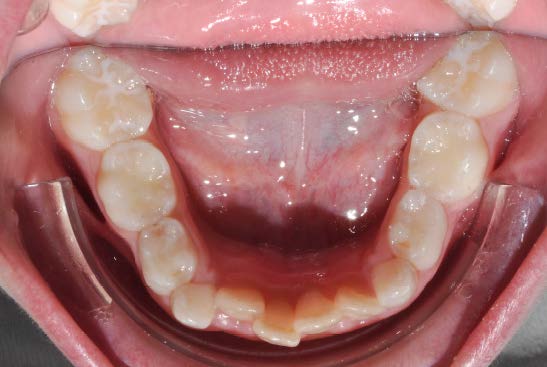

The patient presented with a skeletal Class I relationship and a mesofacial growth pattern, indicating balanced sagittal and vertical skeletal proportions. Dental examination revealed a Class I molar and canine relationship bilaterally. The patient was in the mixed dentition phase. Significant dental crowding was observed in both arches, consistent with a dentoalveolar discrepancy. Midline deviations were present, affecting dental symmetry and occlusal harmony. The maxillary lateral incisors were in crossbite, contributing to anterior transverse discrepancy and functional imbalance.

Periodontal evaluation revealed early signs of periodontal disease, primarily affecting tooth 41. Radiographic assessment demonstrated root convergence of teeth 11 and 21, indicating compromised root parallelism. Overall, the initial presentation was characterized by dentoalveolar crowding, transverse discrepancies, occlusal asymmetries, and early periodontal involvement within an otherwise favorable skeletal framework, requiring a carefully planned orthodontic approach to ensure functional stability and periodontal preservation.